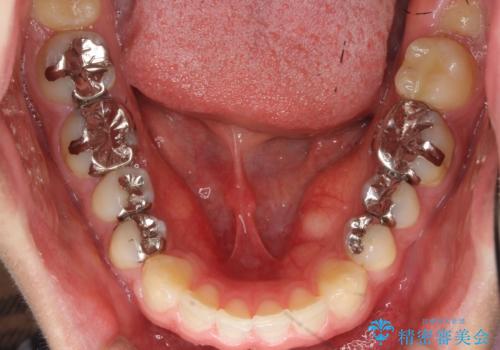

奥歯のかみあわせも問題なく、また、下の前歯のがたつきが元からない場合は上の部分矯正が十分可能です。

上下親知らずの抜歯や虫歯処置も矯正前後で行っています。